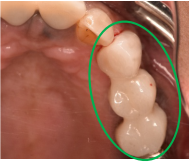

女性Hさん 60代(オールセラミック冠・インプラント)

主訴

右下のブリッジがゆらゆら動く。

治療内容

ブリッジの支台になっている奥の歯が、被せ物の中で虫歯になり、支台の役割を果たさず、前方の歯のみで支えられていました。前方の歯をそのままにして、後方の部分を切り離すと、そのまま取れてきました。中は、虫歯で歯根しか残っていない状況でした。この歯は、根管治療後、単独でオールセラミック冠を被せ、歯のないところにインプラントを埋入しました。

所感

今回の治療法には、次の3つの方法があります。

(1)虫歯になっていた歯の根管治療をし、土台を入れ、また再びブリッジにする。しかし、虫歯になっていたほうの歯は、ブリッジの支台として使うには、心もとなく長持ちしない可能性が高く、今度問題が生じたときには抜歯になる。

(2)虫歯になっていた歯に、単独で被せ物をし、歯のないところに1本だけの部分入れ歯を入れる。取り外しの入れ歯なので、自分の歯のような感覚で噛むことはできない。この方法も歯のない部分の負担を欠損の両側の歯に負担してもらうため、長持ちしない可能性が高い。

(3)虫歯になっていた歯に、単独で被せ物をし、歯のないところにインプラントを埋入する。欠損している部分の負担を前後の歯に負担させないので、歯を守ることができる。また、自分の歯と同じ感覚で食事をすることができる。

患者さんは、3つ目の方法を選択されました。一番長持ちし、これ以上歯を失わないためには、最良の方法だと考えます。

オールセラミック冠(失活歯):¥104,500(税込)

インプラント:¥363,000(税込)

合計:¥467,500(税込)

Before

冠の中で大きな虫歯になり支台の役割を果たしていませんでした。

【インプラント埋入前】

冠はブリッジを切断しただけで取れてきました。軟化象牙質を取り除いたところ、歯根しか残っていない状況で保存できるかどうかのぎりぎりのところでした。

After